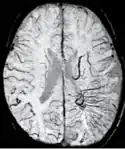

SWI venogram of a neonate with Sturge–Weber syndrome

An SWI venogram of a neonate with Sturge–Weber syndrome who did not display neurological symptoms is shown to the right. The initial conventional MR imaging methods did not demonstrate any abnormality. The abnormal venous vasculature in the left occipital lobe extending between the posterior horn of the ventricle and the cortical surface is clearly visible in the venogram. Due to the high resolution even collaterals can be resolved.